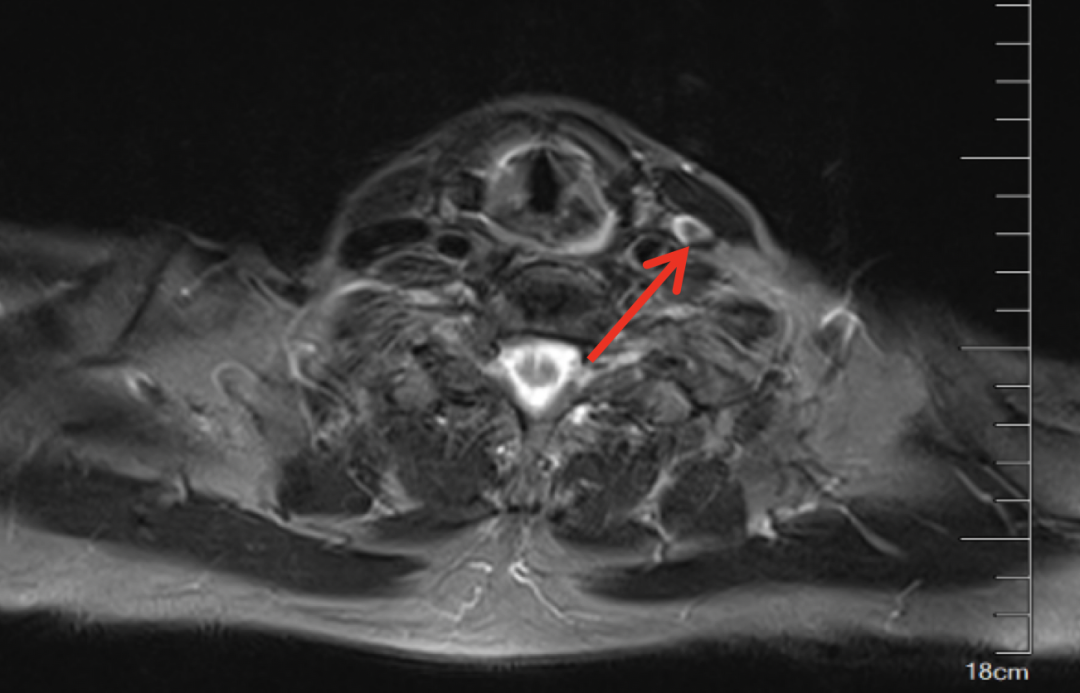

图片

2020年5月CT示左侧颈部肿块大小约1.0cm

疗效评价PR